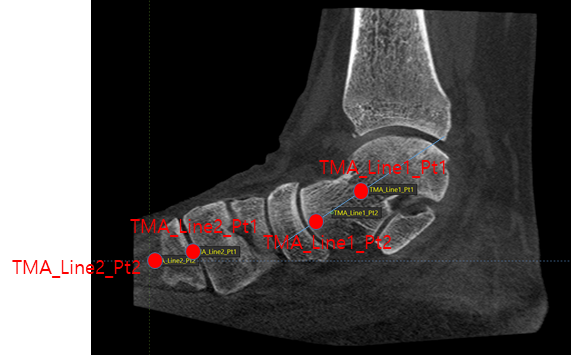

- 질환 진단 보조에 활용할 족부 각도 추정을 위한 랜드마크 포인트 데이터 예측 모델 개발

- 평발, 요족 등의 족부 질환과 발목 관절염등의 족관절 질환 진단과정에서, Talo-1st metatarsal angle 등 아래에 명시한 특정 각도들을 이용하여 이를 보조할 수 있음

- 족부 각도 추정을 위해선 각도를 측정하는 기준인 랜드마크 포인트가 필요하며 이를 위해 각도 추정을 위한 랜드마크 포인트 예측 모델을 개발

- 주요 병변들과 연관된 각도들(calcaneal pitch angle, Talo-1st metatarsal angle (TMA), Talo-calcaneal angle (TCA), Hindfoot alignment angle (HAA), Medial talar articular surface angle (MTASA) 등)을 추정하기 위한 랜드마크 포인트 예측 모델 개발

- GU2Net 기반 모델에 원본 이미지, 랜드마크 포인트를 학습 데이터 셋으로 활용하며, 최종적으로 이미지를 넣었을 때 랜드마크 포인트를 출력하는 인공지능 모델 개발

- 공개된 연구 중 제안하는 task와 완전히 동일한 데이터와 모델은 없으며 이에 따라 유사한 task를 수행하는 연구를 기준으로 모델을 선정

- GU2Net은 U-Net기반의 모델로 최근 손, 폐, 머리 등의 Xray 데이터셋에서의 랜드마크 포인트 추정연구에서 좋은 성능을 내고 있어 해당 모델을 Baseline 모델로 선정